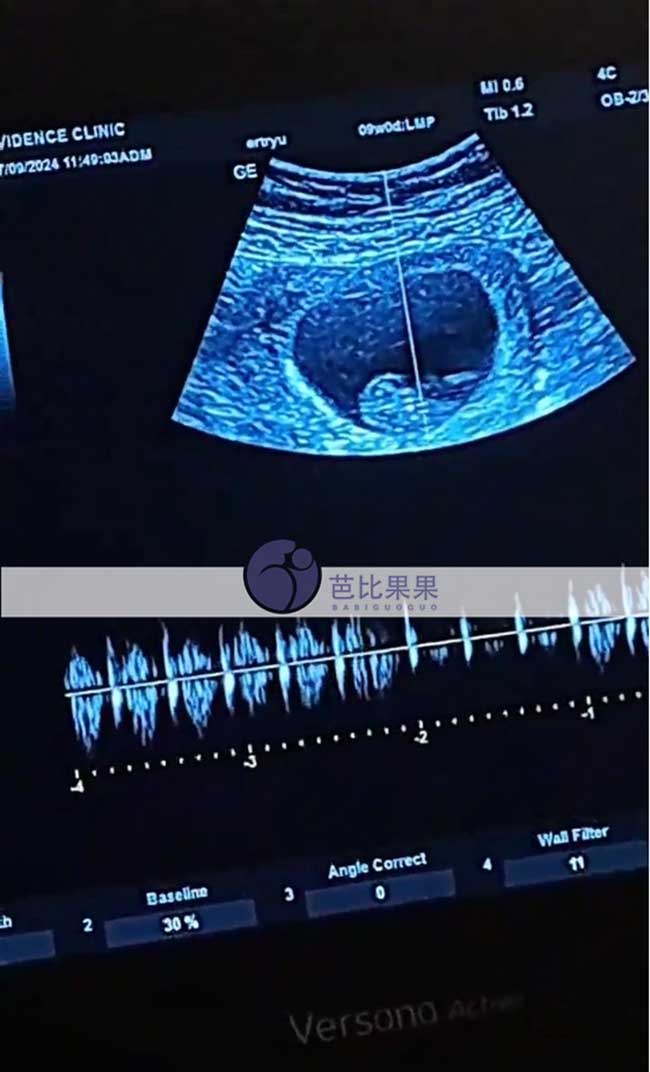

Z先生家的试管妈妈在格鲁吉亚silk医院做孕9周B超

Z先生家的试管妈妈在格鲁吉亚silk医院做孕9周B超,胎心正常发育着~